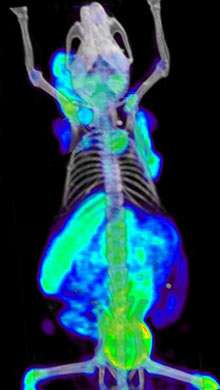

Dopo molteplici prove, i luminari hanno ottenuto una scansione il cui grafico somiglia molto ad una heat map , dunque una grafica che, in base al colore e all’intensità, offre una rappresentazione visiva della concentrazione di cellule sotto esame, in tutte le aree sottoposte a scansione (vedi figura).